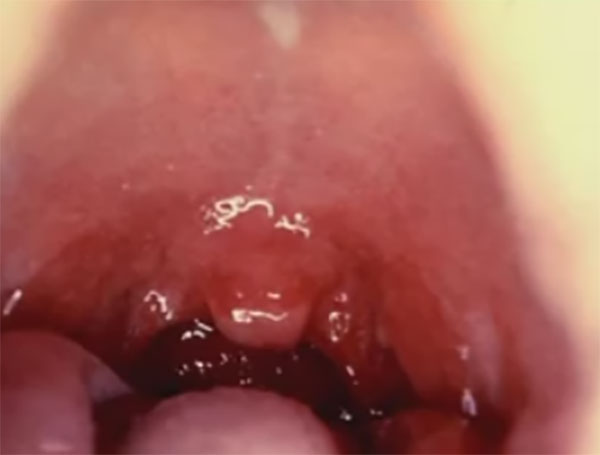

Предлагаю вашему вниманию иллюстрацию того, как выглядит дифтерия у детей, фото:

В зависимости от того, какой участок тела ребенка был поражен микроорганизмами, присутствуют отличительные признаки проявления недуга.

Как выглядит горло при дифтерии?

Слизистые оболочки горла краснеют, и на них образуется налёт серо-белого цвета в виде плёнки, которая отделяется с трудом, обнажая кровоточащую поверхность. В зависимости от формы болезни плёнка может покрывать миндалину полностью, а может — только частично.